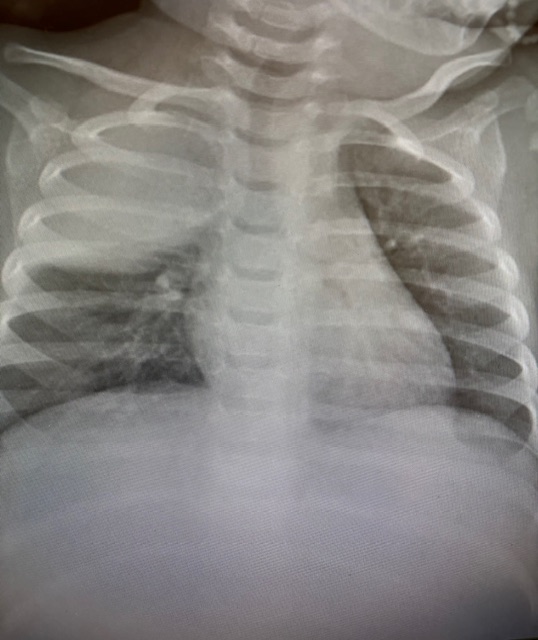

- Vacinação em dia: Melhor forma de prevenção!!! Doenças como influenza, sarampo, caxumba, rubéola, hepatite A e B, meningites, pneumonia, diarreia por Rotavírus, Covid, catapora.